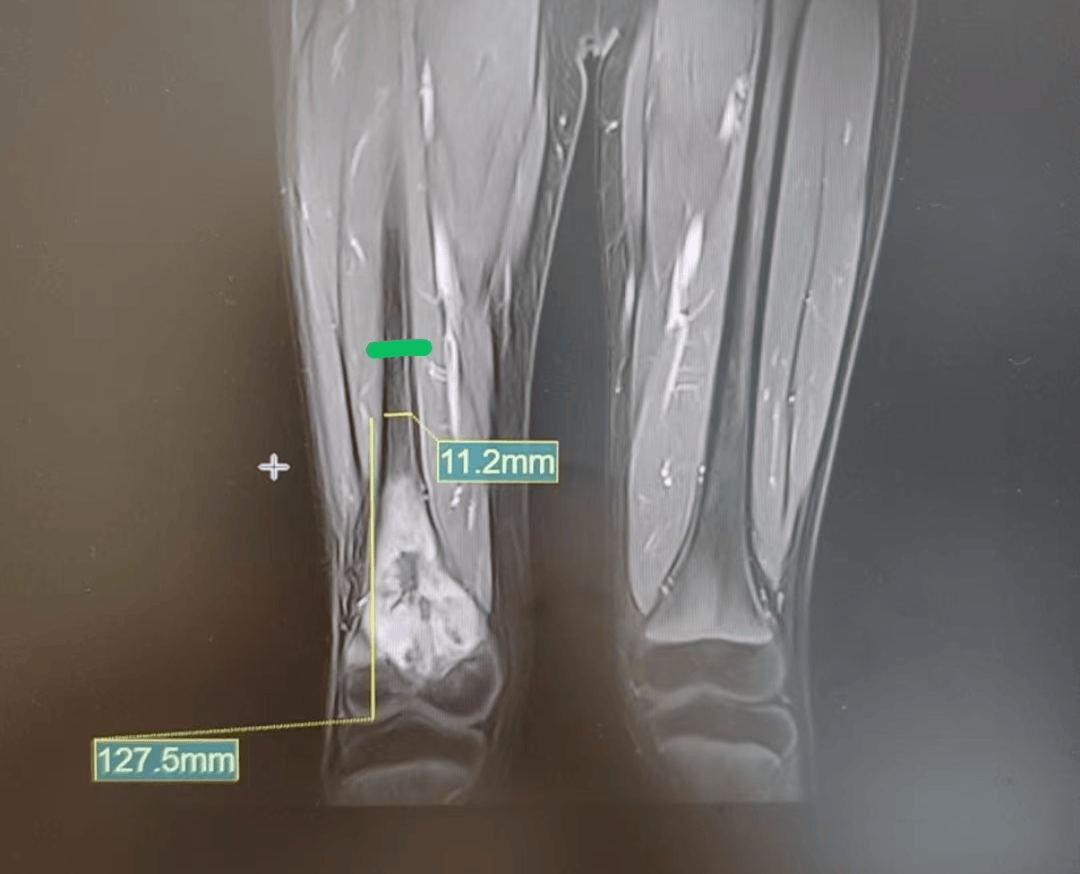

检查结果犹如晴天霹雳:X片显示小宇的右侧股骨内侧干骺端异常密度;MRI提示右侧股骨占位性病变。“医生告诉我们,孩子可能是骨癌,情况不太乐观,建议立即转诊到更专业的儿童医院。”小宇妈妈说。

在浙大儿院三维重建CT检查后,医生发现小宇的右股骨干骺端及骨骺大片骨质破坏伴软组织肿块。